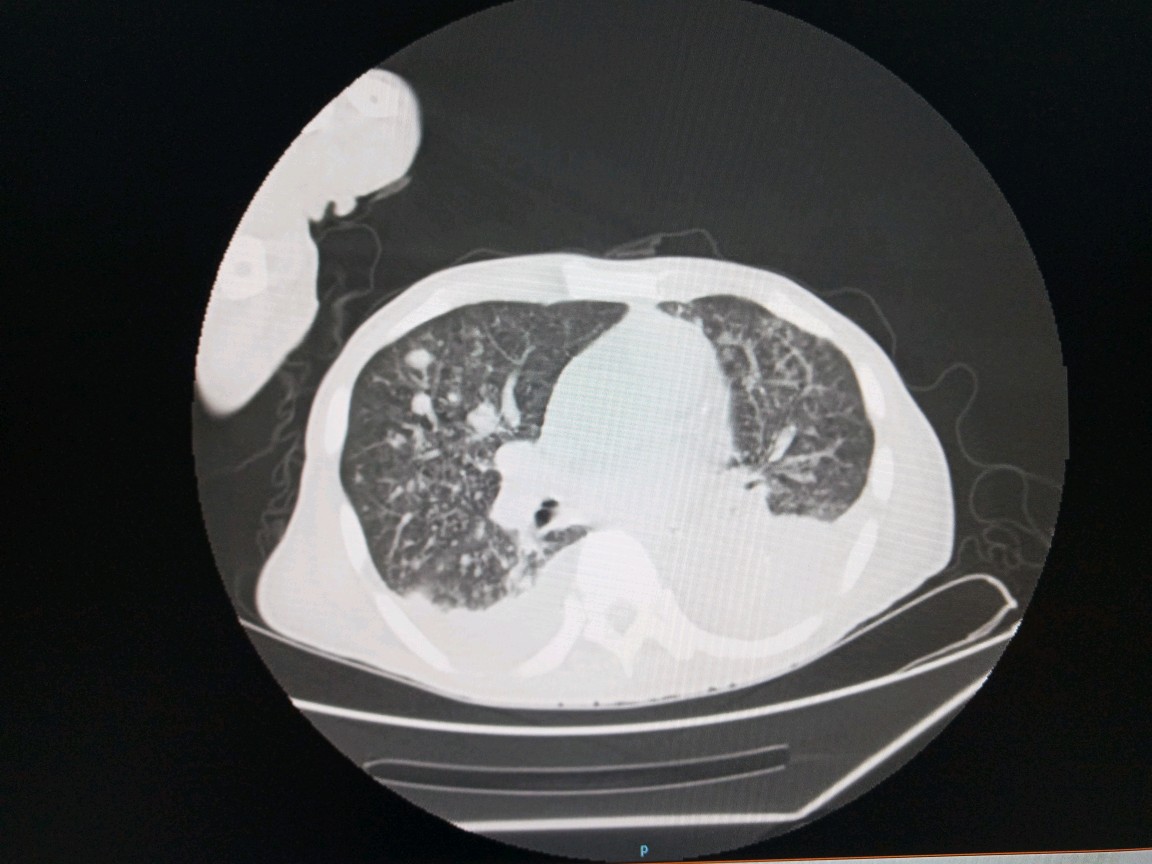

进一步完成胸部和腹部CT检查发现。不光是骨头有转移,肺上多发的转移瘤。右侧的肾上腺也有转移。